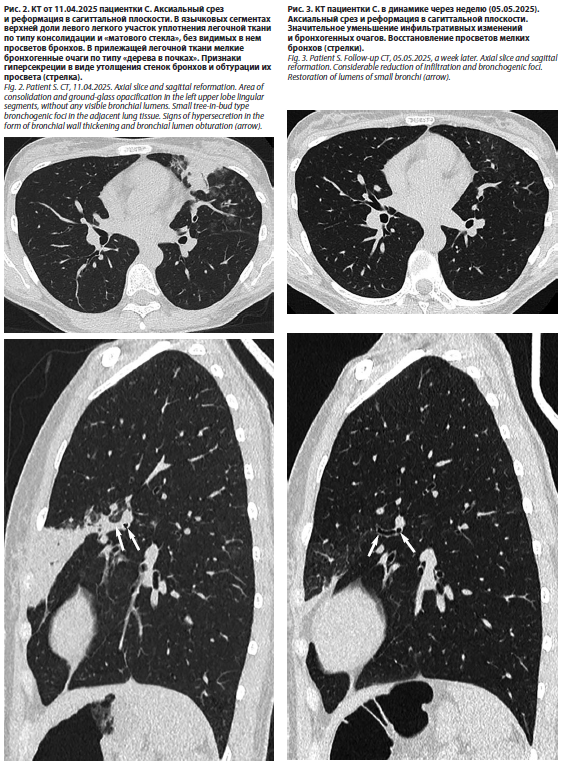

Не противоречили этому диагнозу и результаты КТ-исследования от 11.04.2025 (рис. 2).

При оценке результатов КТ органов грудной клетки в динамике был отмечен регресс очагово-инфильтративных изменений в левом легком (рис. 3).

Позднее были получены результаты лабораторных исследований, подтвердившие высказанное предположение о микоплазменной этиологии пневмонии. Антитела к M. pneumoniae от 12.04.2025: IgG – коэффициент позитивности 0,01 (отрицательный результат), IgM – коэффициент позитивности 5,7 (положительный результат). Метод качественной ПЦР (мазок слизистой ротоглотки) от 13.04.2025 – выявлена ДНК M. pneumoniae. Антитела к M. pneumoniae (иммуноферментный анализ) 05.05.2025 – IgG 4 УЕ, IgM 3,05 УЕ.При оценке результатов КТ органов грудной клетки в динамике был отмечен регресс очагово-инфильтративных изменений в левом легком (рис. 3).